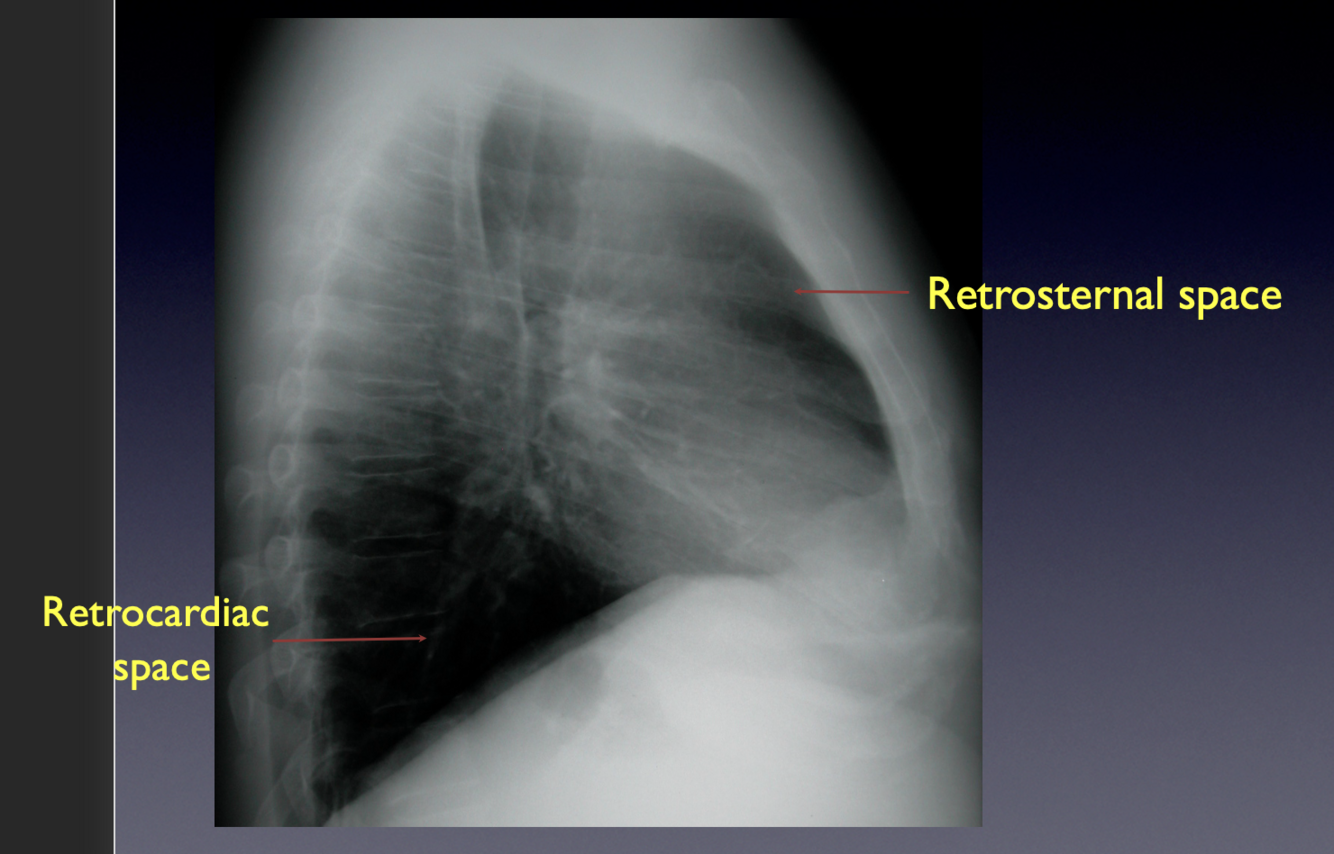

13

Go

A

The retrosternal and retrocardiac spaces should be dark on a lateral CXR.

-If they are not, disease is present

Normal CXR